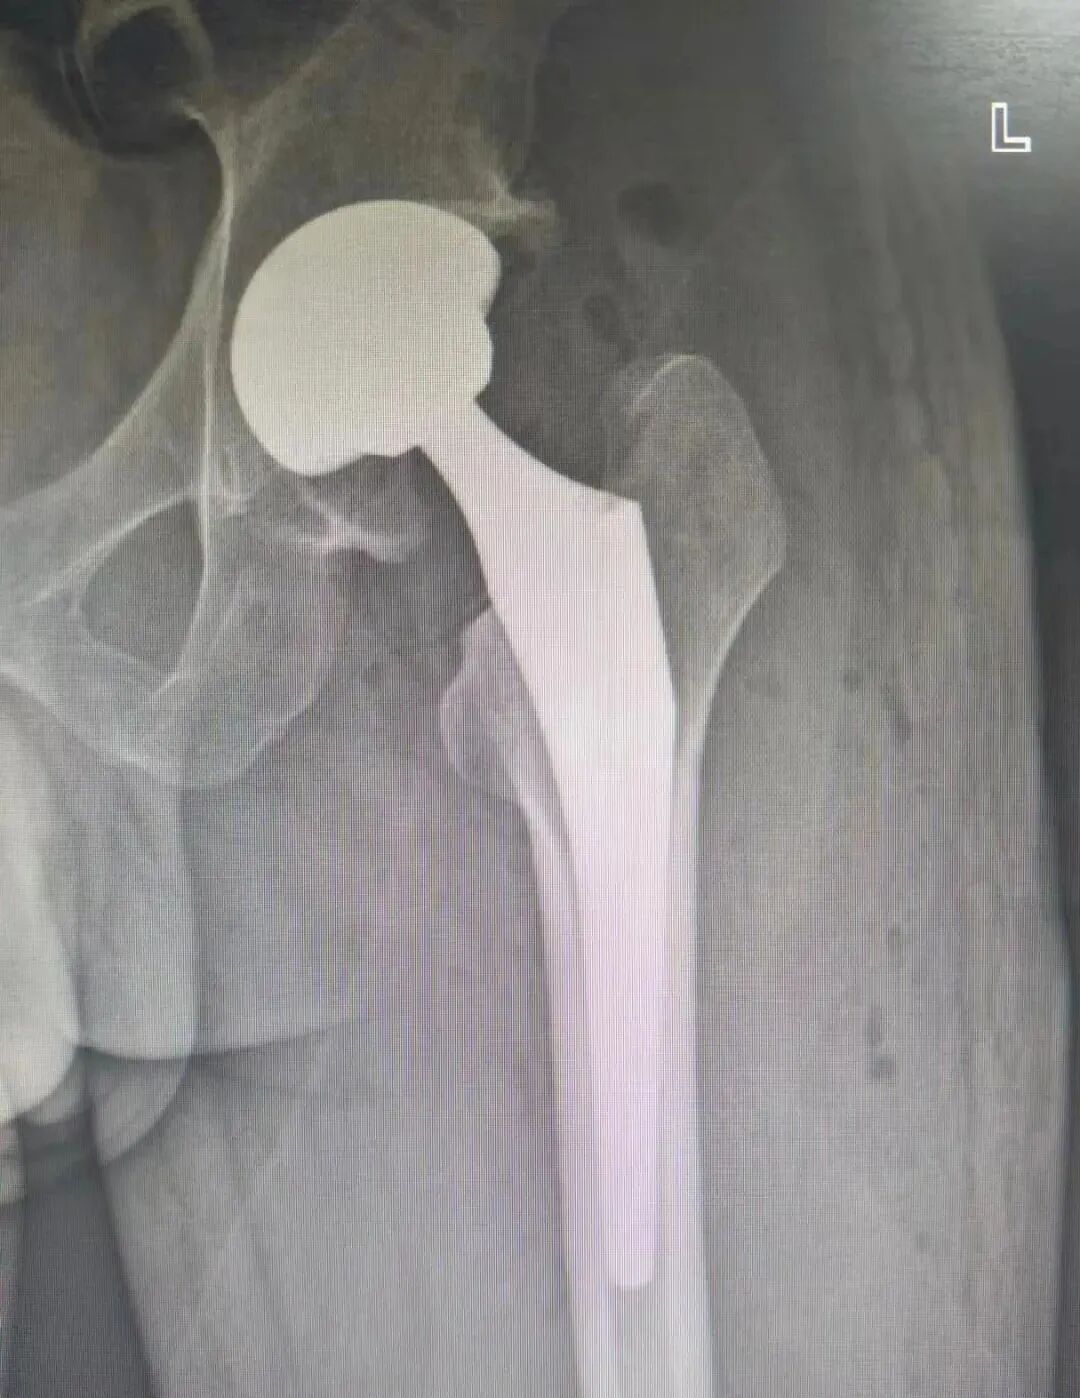

51岁杨某,以”左髋部疼痛伴活动受限多年”主诉入院。入院诊断:左侧股骨头坏死Ⅳ期;神经性皮。骨科鞠健主任团队为患者行左侧全髋关节置换术,其中骨科高值耗材费用从集采前的2.3万元左右,降到了集采后的8500元左右,大大减轻了患者经济负担。

患者术前